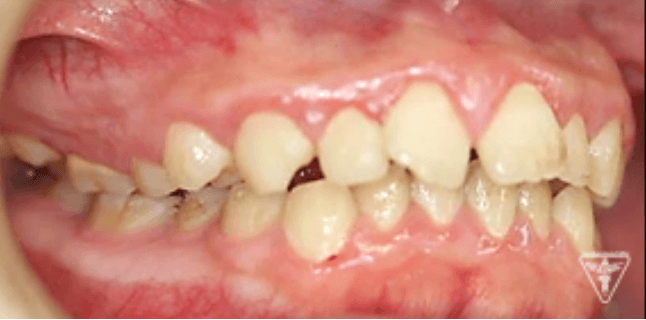

治療前後の比較

治療前